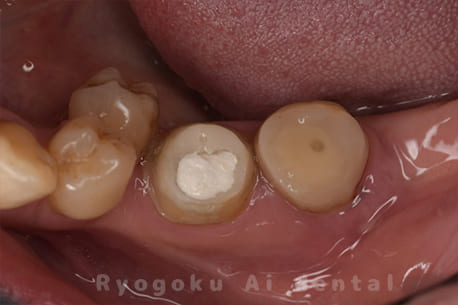

左下が腫れているとのことで来院された患者さんです。根の先に病気を作っているため、マイクロスコープを使用した治療を提案し、進めていきました。現在も経過良好です。

<リスク・副作用>

術後は痛み、腫れ、痺れなどの副作用が生じる場合があります。症状が再発する可能性があります。